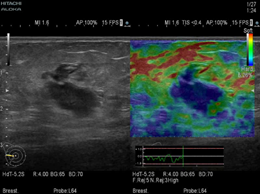

(Real-time Tissue Elastography?)

作为应用zei完善、覆盖zei全面的实时组织弹性成像技术,日立组织开展了国内zei早的弹性成像多中心研究项目,率先规范化、标准化。同时,日立弹性也在不断提升和优化,交响系列全新推出FLR、ASF等智能化测量技术,更精确高效的服务于临床诊断。

ET技术在“交响”平台上全面提升,实现强大的信息处理能力,能够对不同阶段的血管病变进行定量分析,早期干预,早期治疗。